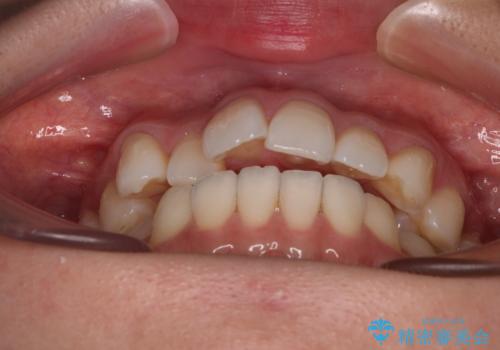

- 前歯のデコボコと、上下前歯が接触せずに前に飛び出していることを気にして来院された患者様です。

舌の突出癖が強く、それが原因で上顎歯列全体が前方に突出し、上下前歯が接触できない状態となっていました。

補助装置を用いて上顎臼歯を後方移動させ、歯列を整えながら前歯部の接触を図ることとしました。

舌の突出癖改善のためのトレーニングを指導しながら、ワイヤー装置にて矯正治療を行うこととしました。